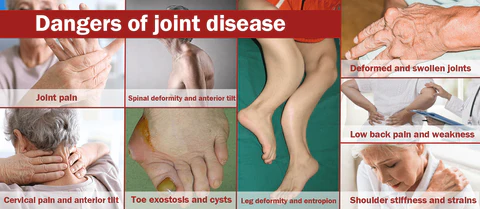

Orthopedic diseases can occur due to a variety of factors, including age-related degeneration, overuse or injury, genetics, and certain medical conditions such as diabetes or rheumatoid arthritis. Poor posture, poor nutrition, and certain types of work or sports can also increase the risk of developing an orthopedic condition. According to statistics, 35% of the population in the US and Europe suffer from joint problems, with varying degrees of joint problems in every five people. The milder cases include arthritis, rheumatism, and gout, with symptoms such as pain, stiffness, swelling, difficulty in movement, fatigue, and loss of range of motion. Severe cases can result in joint deformities, fever, and intense joint pain, which can lead to long-term pain and disability. In extreme cases, orthopedic diseases can even lead to life-threatening complications.